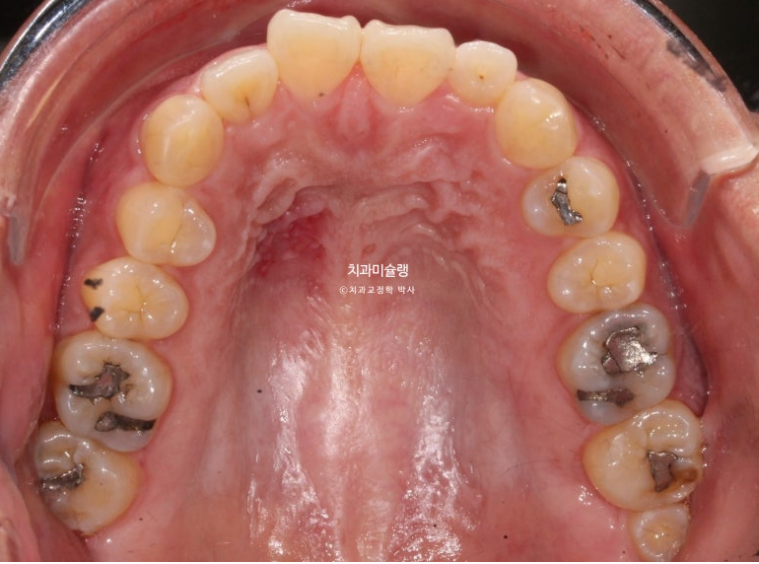

The bone in the gum area above the front teeth looks uneven, right?

I’ll explain the reason in a moment.

If you compare the before-and-after photos, you can see that the previously flat gum area above the front teeth has become uneven.

2022.12~2025.12

It is easy to misunderstand this as bone growing and protruding more than before, but in fact, the protruding part is the original position of the bone from before treatment, when the gums were protruding.

When the front teeth are successfully moved backward, including the roots, the gum bone covering the tooth roots also naturally resorbs and moves backward together with the roots. This is the process by which gum protrusion is resolved.

However, some areas of gum bone stubbornly remain in their original position and do not resorb.

As a result, these areas can look relatively protruded compared with the surrounding area after treatment, and this is the reason why the gums sometimes look uneven after extraction orthodontics.

There is no need to worry too much. Over time, most of it naturally becomes flatter through bone remodeling.

Although we do not recommend it, if this area really bothers you, the gums can be opened and the bone can be shaved down to make it flatter.